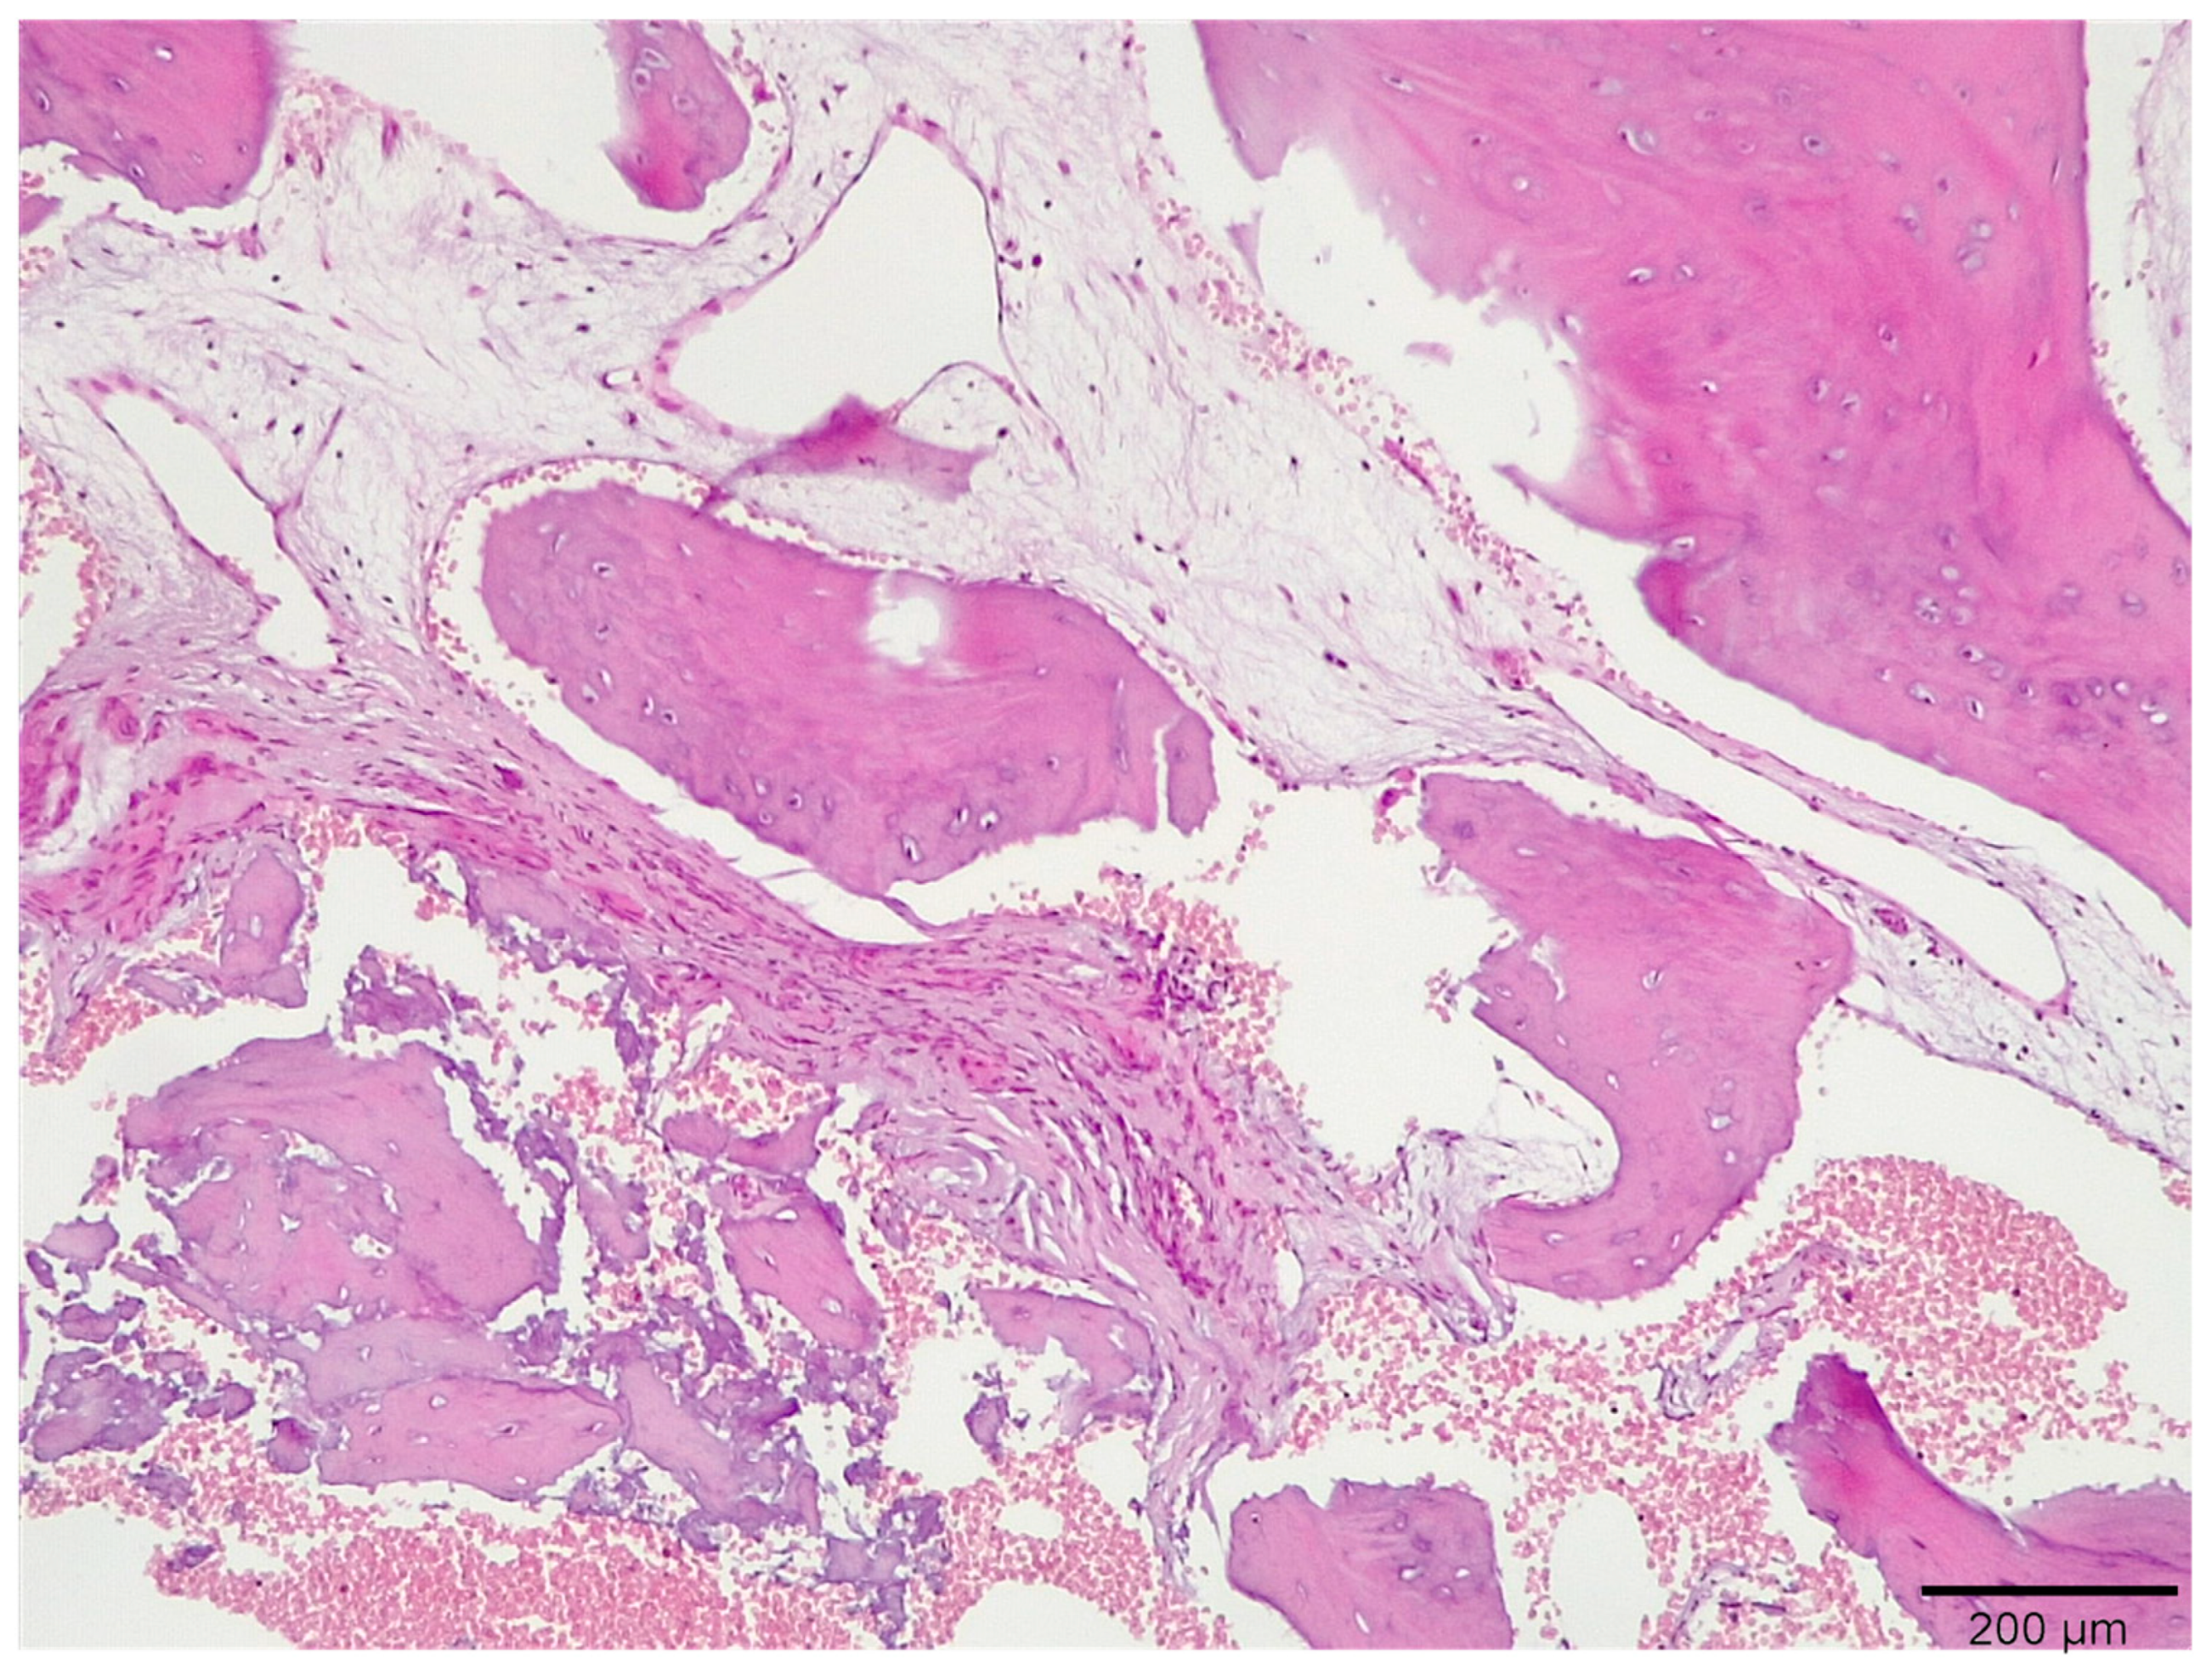

3.1. Histological Analysis Showed Signs of New Bone Formation at 60 Days

3.2. Histologic Data Obtained after Samples Analysis at 24 Months of Evaluation

| New bone | 16.3 ± 1.98 | 41.1 ± 0.76 | 54.5 ± 0.24 | 59.4 ± 1.23 * |

| Residual Graft | 37.1 ± 0.34 | 30.0 ± 0.45 | 21.3 ± 0.88 | 15.6 ± 086 |

| Connective tissue | 46.6 ± 0.11 | 29.9 ± 0.56 | 24.2 ± 0.32 | 25.0 ± 0.44 |